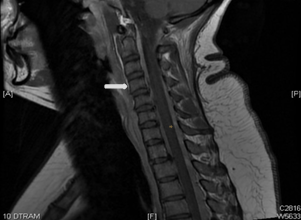

She had MRI brain and C spine with contrast, (Figure 1) a lumbar puncture after imaging, intravenous pain medication, dexamethasone per os, and was positioned supinely. Her brain MRI and C spine showed signs of low intracranial pressure with DME; see in Figure 2. She initially had a traumatic and dry LP with Glucose 5.68, raised protein of 3672 mg, 54000 red cells, 43 white cells and xanthochromia was positive.

Figure 2 white arrows pointing to contrast enhancement.